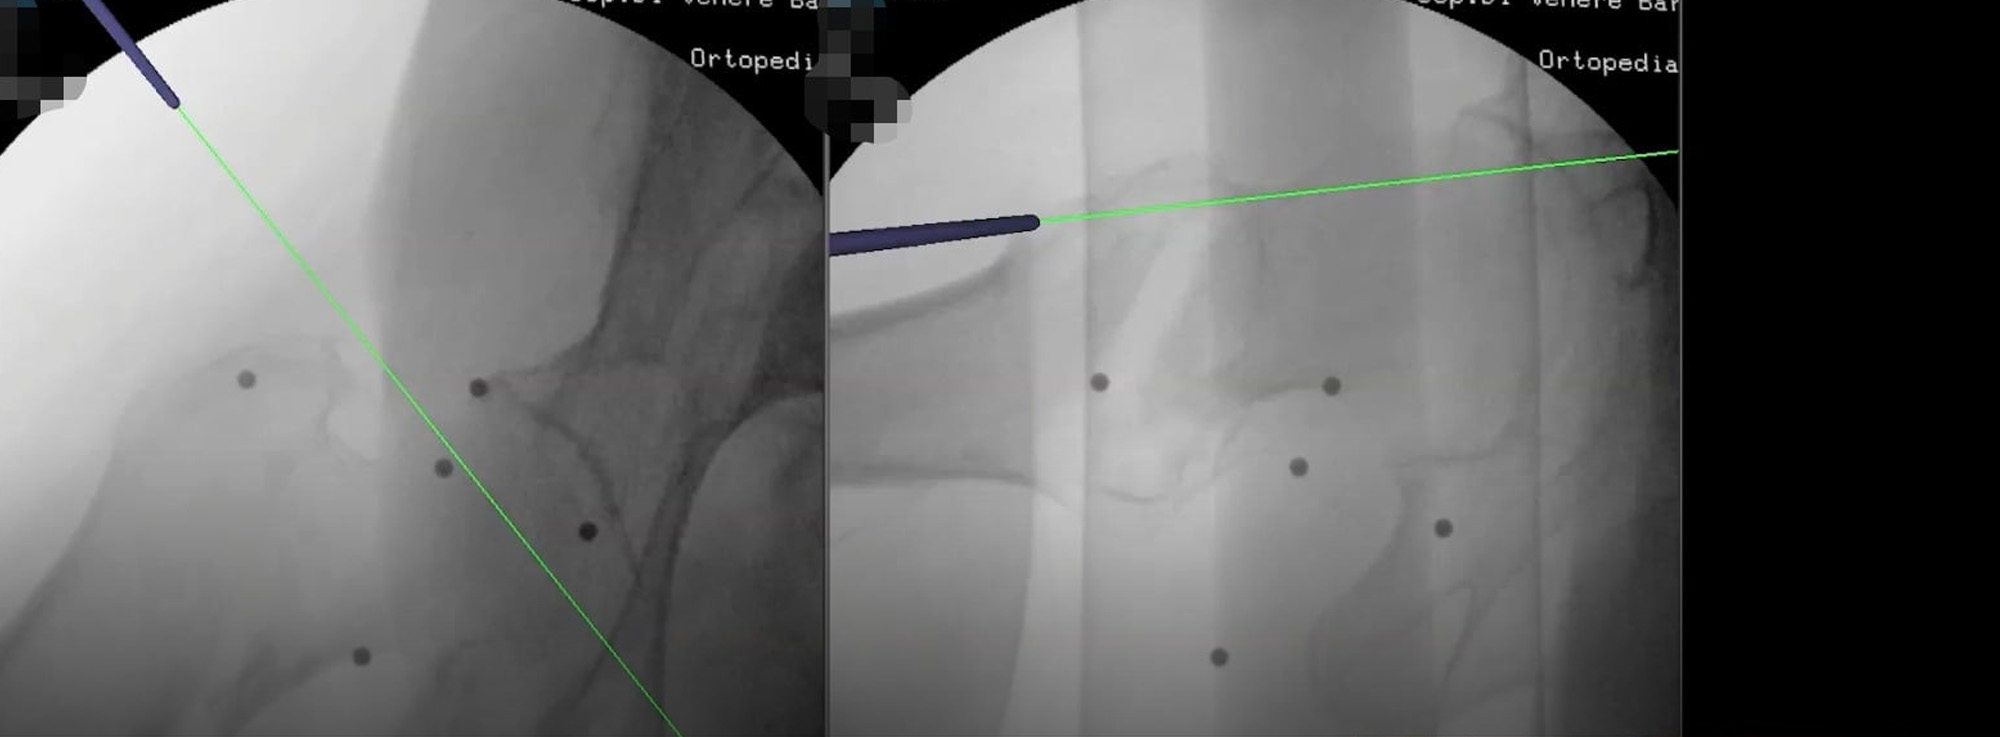

La novità è racchiusa nell’acronimo EBANAV (Endovis Bio Advanced NAVigator), un sistema di navigazione virtuale che permette ai chirurghi ortopedici di visualizzare il campo operatorio in tre dimensioni e a 360 gradi, con notevoli vantaggi in termini di precisione millimetrica e quindi di azzeramento dei margini d’errore, riduzione delle radiazioni ionizzanti, oltre a tempi d’intervento – circa 25 minuti – ridotti e resi omogenei rispetto alle tecniche tradizionali.

Grazie ad una unità di elaborazione e visualizzazione computerizzata e al posizionamento – assolutamente non invasivo – di un sistema di sensori al paziente, all’amplificatore di brillanza (l’apparecchiatura radiologica che permette di visualizzare l’arto su cui intervenire) e allo strumentario, l’ambiente operatorio viene trasposto dal mondo reale a quello virtuale. «L’ortopedico – spiega il dr. Caiaffa – in sostanza può operare guardando un monitor sul quale vengono riprodotte immagini in continuo e in tre dimensioni dell’articolazione, evitando i macchinosi passaggi da un’immagine fissa all’altra della tecnica tradizionale».

Ridurre la frattura e stabilizzarla con il chiodo diventa così un’operazione più semplice, in cui i “limiti” umani dell’operatore vengono superati dalla navigazione virtuale, capace di guidare l’atto chirurgico con la riproduzione in 3D, estremamente precisa, del posizionamento del mezzo di sintesi. La realtà virtuale, in tal modo, permette di vedere in ogni momento dove è collocato il nostro sistema nello spazio e rispetto alla frattura del paziente, oltre che consentire un’alta predittività delle misure dell’impianto.